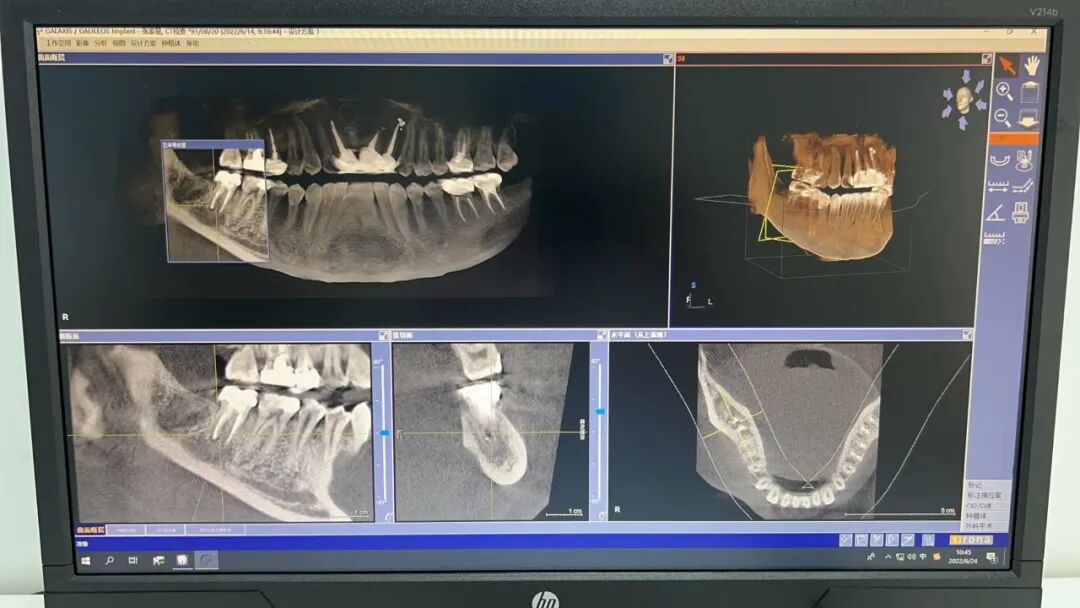

口腔ct怎么拍摄【医院动态】口腔科的“火眼金睛”——CBCT投入使用_https://www.jmylbn.com_新闻资讯_第5张(绿色线条为下颌神经管)

2. 口腔CT(锥形束CT):可从三维角度对组织情况进行反映,准确清晰地诊查各组织的健康状态,病损范围及与周围组织间的关系以及发现更加细微的病变,诊查各类阻生牙的位置状态及与临近的神经和窦腔的位置距离,协助医师们在进行术前方案设计以及术后科学评价,还可清晰地检查牙槽骨内的病损。

口腔ct怎么拍摄【医院动态】口腔科的“火眼金睛”——CBCT投入使用_https://www.jmylbn.com_新闻资讯_第6张